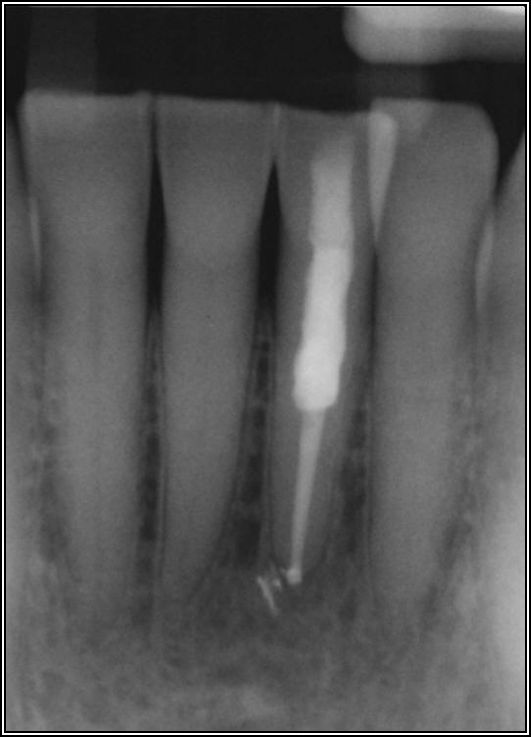

The rules for placement of a post depend on good retention: the greater the length, the greater the retention.3 Also, two-thirds of the length of the root is ideal, but 4 to 5 mm of apical gutta-percha is essential because anything less than that will disrupt the seal.8 Figure 14 shows a case where a patient had a post, core, and crown. The threaded post was shorter than ideal because the tooth was longer. Not visible was the mental foramen underneath. The patient did not have the financial resources to have the case redone. However, when the post would be removed, the clinician would need to trephine or use an ultrasonic around it, making the access bigger than an ideal conservative access. Potentially, the crown would come off. The patient did not have finances for re-treating the tooth and could not have an apicoectomy because the mental foramen was directly under the tooth.

The options, therefore, were to extract it and put a bridge or an implant in later when funds were acquired, or, as was done in this case, perform an intentional replant. The clinician extracted the tooth, cut it, placed MTA, and then put it back under occlusion using sutures—although the clinician would normally put composite in each corner to maintain it and would not etch. Usually after 2 weeks, there is stability. Figure 15 shows the postoperative radiograph, and Figure 16 shows a radiograph 4.5 years later. The patient's probing went from 3 to 4 mm, but overall it was a success because something is always lost coronally, whether the case is a replant or an implant.

Fig 14. The post was shorter than ideal.

Figure 14

Fig 15. Postoperative radiograph.

Figure 15

Fig 16. Radiograph after 4.5 years.

Figure 16